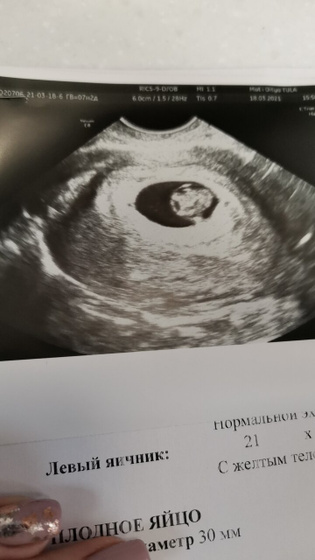

Сегодня увидели эмбриончик, ктр 11 мм, сб+, ритм правильный ЧСС 148 уд. мин, срок 7 недель, 2 дня. Спасибо всем кто писал, переживал?